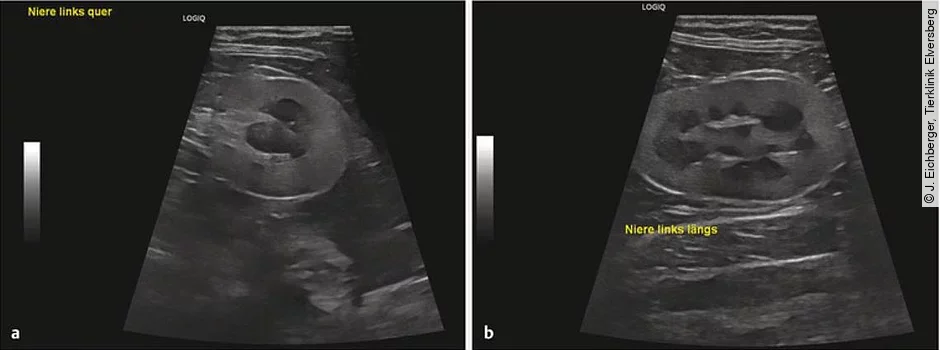

- Bildgebende Diagnostik: Ultraschall ([Abb. 2]) oder Röntgen, um strukturelle Veränderungen, Obstruktionen oder andere Läsionen zu detektieren als Part der initialen Aufarbeitungen; eine Wiederholung der Untersuchung ist vor allem bei unerwarteter Verschlechterung sinnvoll.